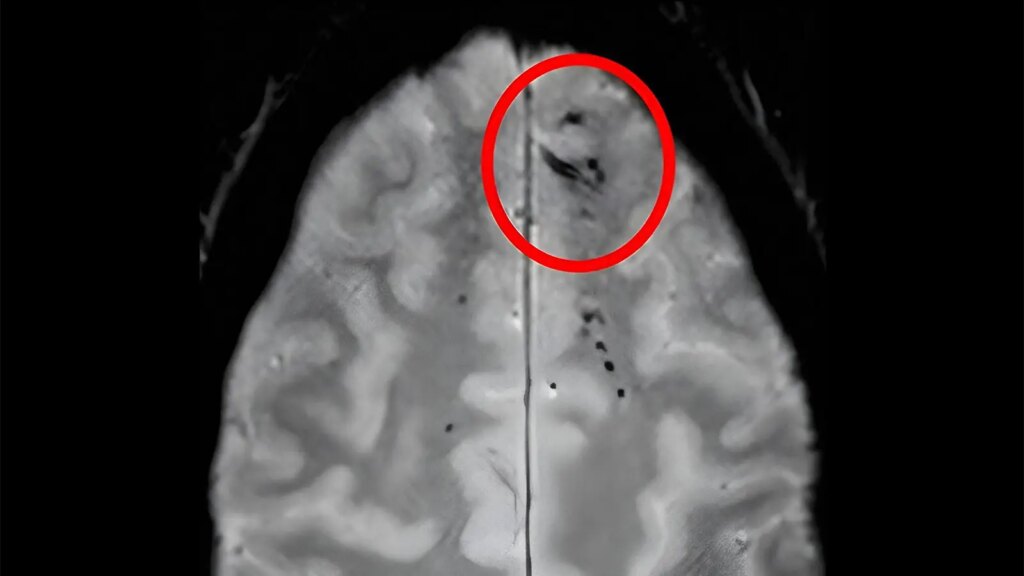

- In a cohort study, brain imaging results showing cerebral microbleeding had varying associations with dementia depending on the specific microbleed pattern.

- An increased risk of dementia was tied to microbleeds in lobar regions, lobar plus subcortical regions, or cortical superficial siderosis only.

- A larger number of microbleeds, regardless of location, was associated with a higher risk of dementia as well.

The location and amount of brain microbleeds that a person has could be telling of their risk of dementia, according to an observational analysis.

Cerebral microbleeds, the neuroimaging findings of small blood product deposits, can be considered a sign of cerebral small vessel disease and have previously been associated with dementia and subsequent stroke. Regarding specific microbleed patterns, prior work suggests that microbleeds in the lobar regions and cortical superficial siderosis are consistent with cerebral amyloid angiopathy (CAA), whereas subcortical microbleeds indicate a hypertensive cause.